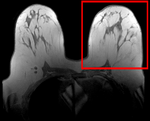

Registration Library Case #6: Breast MRI Treatment Assessment

| fixed image/target pre Rx MRI |

moving image post Rx MRI |

We seek to align the post-treatment (PostRx) scan with the pre-treatment scan to compare local effects (left side only).

unregistered

after affine registration

after nonrigid (BSpline) registration